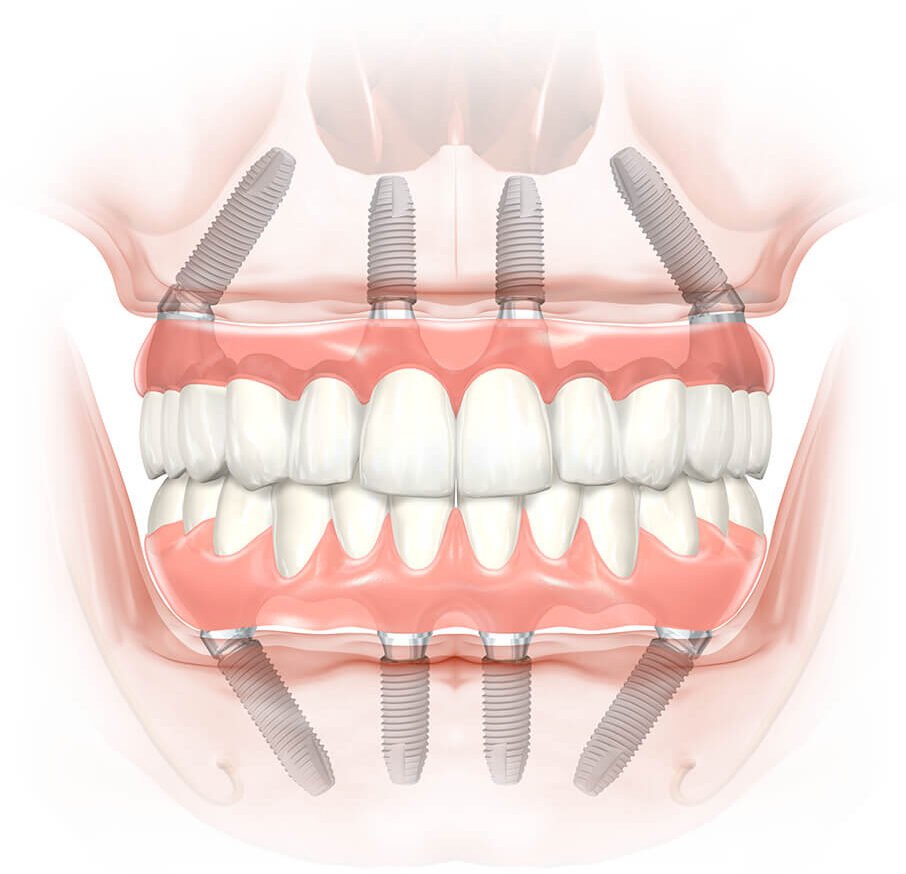

全口重建 All-on-4 一日內就能完成手術,裝上臨時假牙,馬上就能體驗成效!術式原理來自造橋力學,在口腔顎骨植入 4-6 根植體,提供整排牙齒良好的支撐力和穩定性。患者不需經歷傳統植牙 6 個月左右的補骨療程及治療期間缺牙、及需配戴活動假牙等種種不便,是很有效率的治療方案。

▲ All-on-4 全口重建只需植入 4 根植體即可給予整排假牙穩定的支撐力,且手術當天即可安裝臨時假牙。